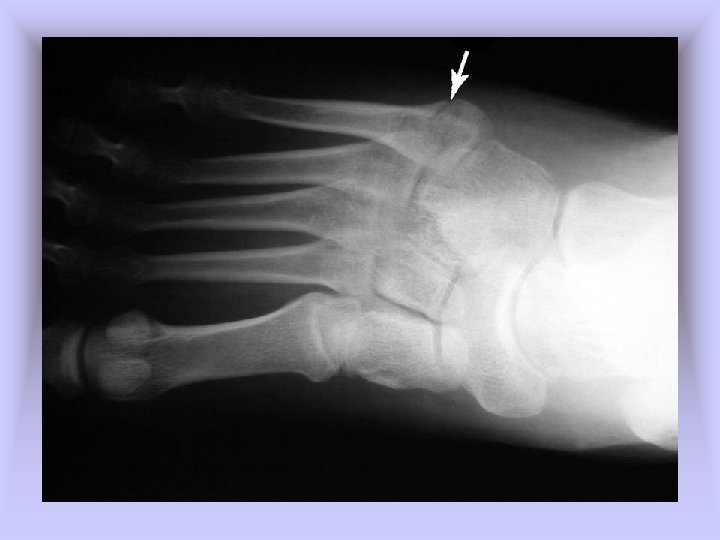

• Metatarsal Stress Fractures – Cause of Injury • 2 nd metatarsal fracture (March fracture) • Change in running pattern, mileage, hills, or hard surfaces • Often the result of structural deformities of the foot or training errors (terrain, footwear, surfaces) • Often associated with Morton’s toe – Signs of Injury • Pain and tenderness along second metatarsal • Pain with running and walking • Continued pain/aching when non-weight bearing

– Care • Determine cause of injury • Generally good success with modified rest and training modifications (pool running, stationary bike) for 2 -4 weeks • Return to running should be gradual over a 2 -3 week period with appropriate shoes